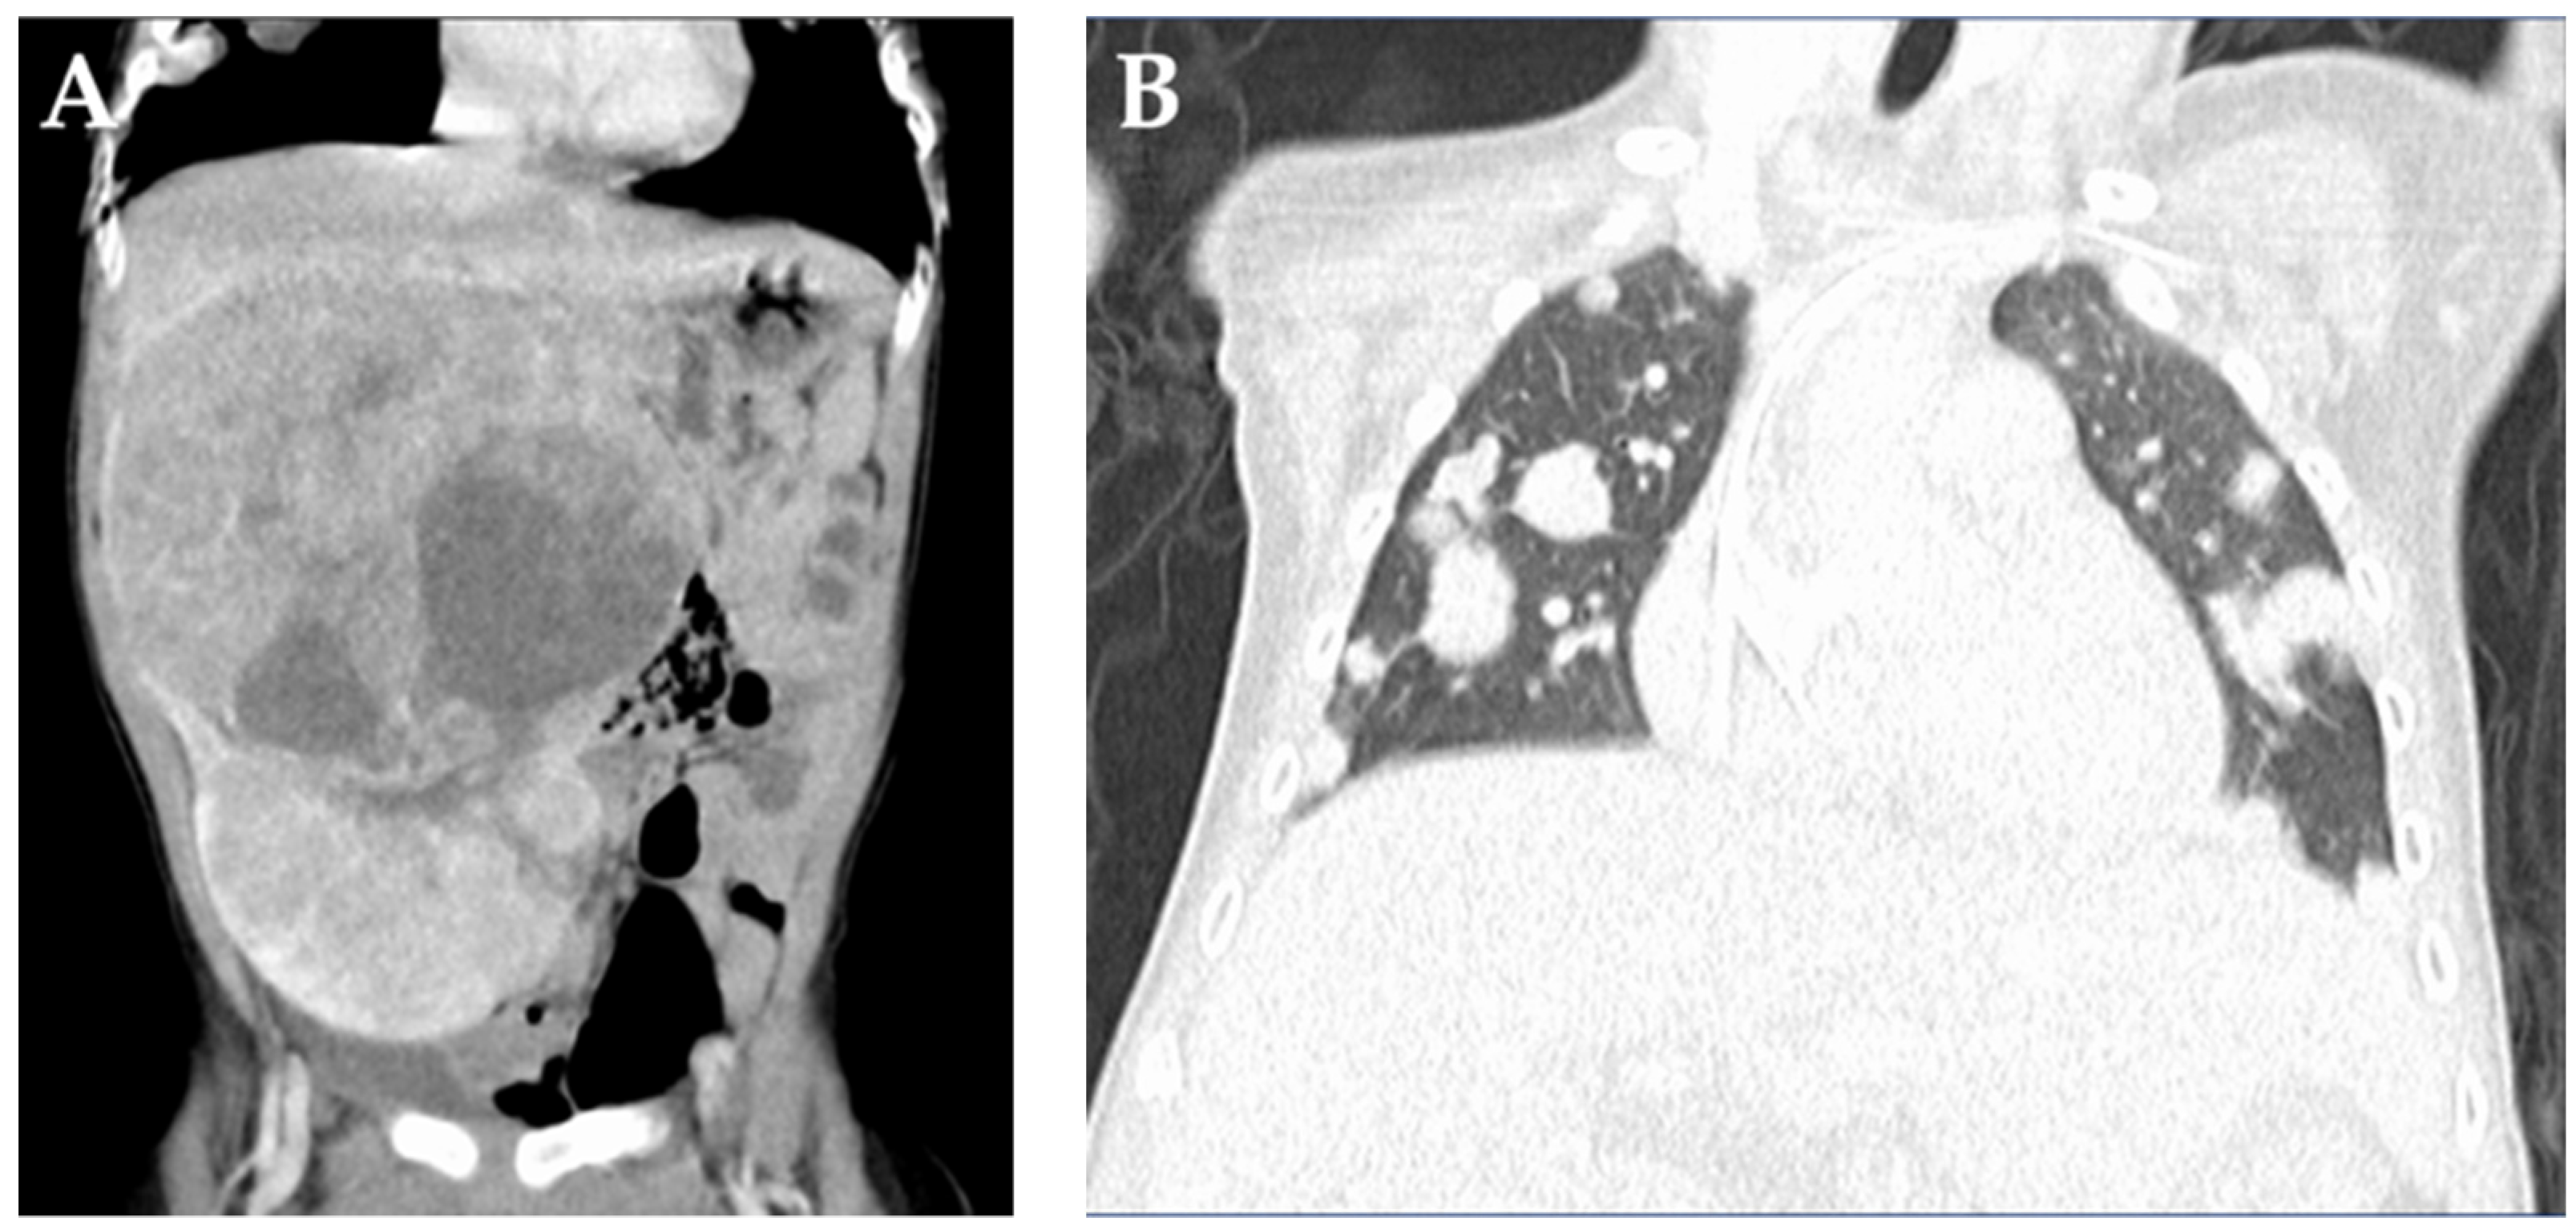

2. Case Report